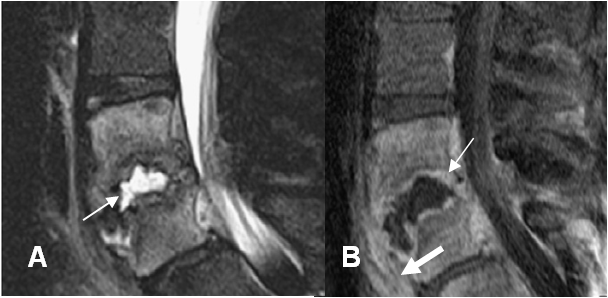

Fig 141 E. Espondilodisquitis. Tomado referencia 57. Igual paciente anterior.

A: RM sagital en STIR. Edema óseo en los cuerpos vertebrales y liquido sobre el disco intervertebral, por espondilodisquitis.

B: RM sagital en T1 con contraste. Realce de los cuerpos vertebrales, las placas terminales (Flecha delgada) y los tejidos blandos prevertebrales (Flecha gruesa), por proceso infeccioso.